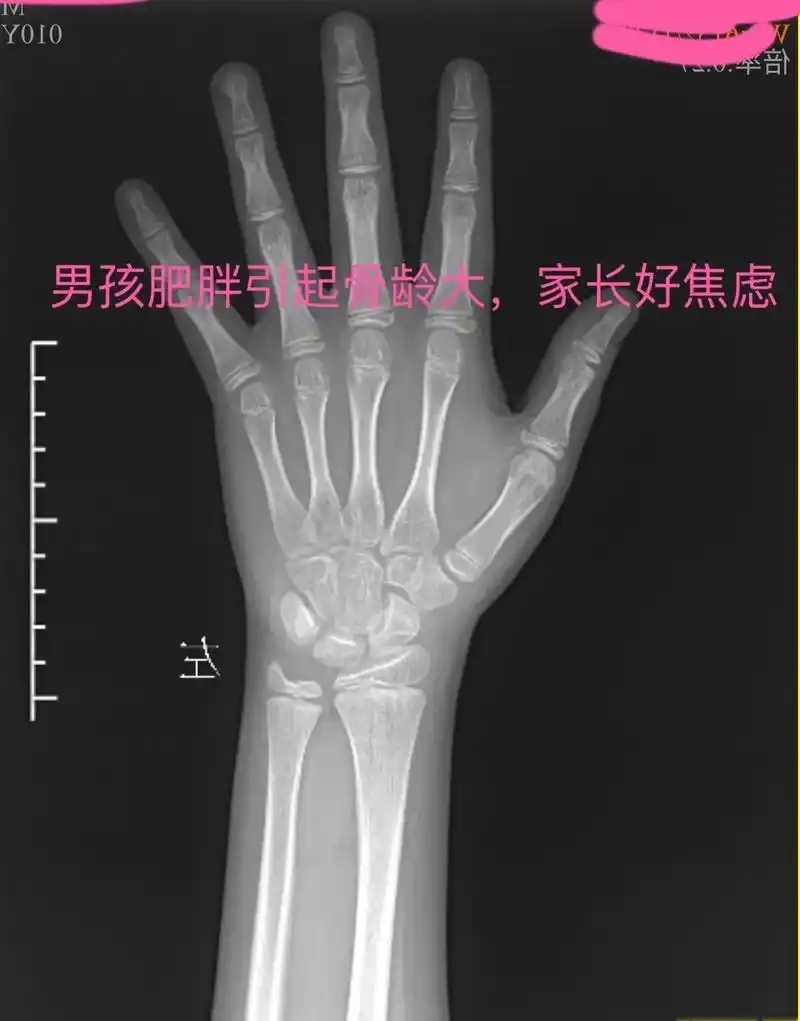

男孩肥胖引起的骨龄大家长很焦虑